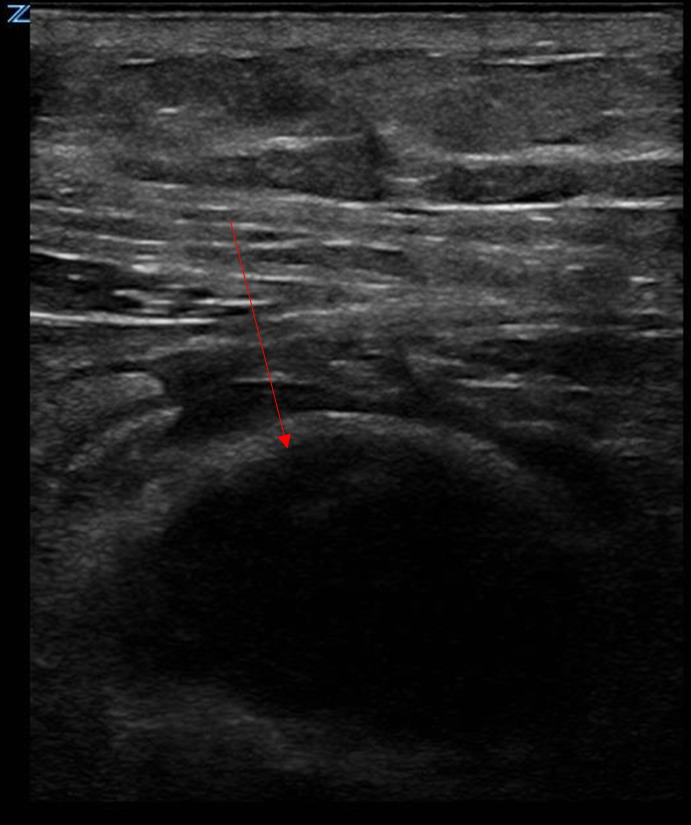

We present a case of a 59-year-old man who arrived to the emergency department with abdominal pain and bruising after coughing. Point of care ultrasound (POCUS) was used to make the diagnosis of rectus sheath hematoma (RSH). This diagnosis was made within minutes of arrival to the ED and subsequently confirmed on computed tomography (CT) of the abdomen. As abdominal ultrasound is a technically straightforward imaging technique which includes a sensitivity that rises about 90%, its utilization to identify rectus sheath hematoma can reduce the rate of CT imaging and time to diagnosis for this pathology.

我们报告了一例 59 岁男子的病例,他因咳嗽后腹痛和瘀伤来到急诊科就诊。急诊超声检查(POCUS)确诊为直肠鞘血肿(RSH)。该诊断是在患者到达急诊室后几分钟内做出的,随后经腹部计算机断层扫描(CT)确诊。由于腹部超声是一种技术简单的成像技术,灵敏度高达 90%,因此利用它来识别直肠鞘血肿可以降低 CT 成像率,缩短诊断时间。